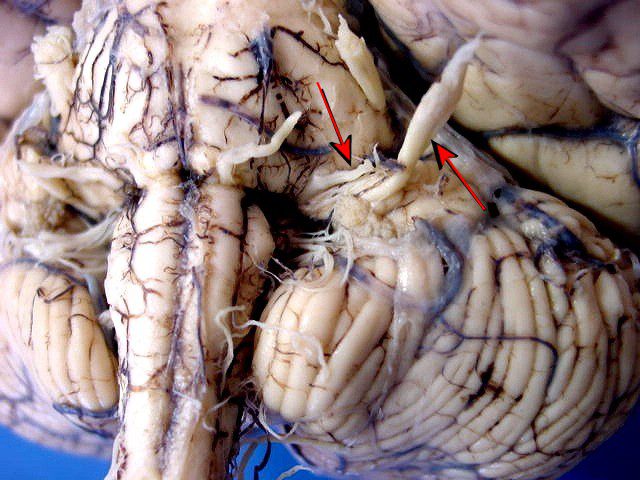

penile nervous system.

Yes. There is a network of nerves inside the penis — nerves that function like electrical wires.

And it is these nerves that send the signal that makes an erection happen.

If the nerves are strong → an erection happens naturally.

If the nerves are weak → the erection fails.

If the nerves are damaged → the erection disappears.

WHY NERVES CONTROL EVERYTHING (AND WHY NO ONE TOLD YOU THIS)

An erection happens in three stages:

⦁ The brain sends the nerve signal.

⦁ The penile nerves receive and amplify this signal.

⦁ The penis reacts with blood, rigidity, and expansion.

Simple.

But here’s the detail that changes everything:

If step 2 fails…

Step 3 never happens.

And this is exactly where 90% of men with ED are failing.

During his studies on peripheral neuropathies (nerve damage), Dr. Mercer noticed that many patients — especially men over 50 — had exactly the same type of nerve degeneration in the pelvic region.

“Nerve degeneration in the penis is one of the first detectable signs of silent neuropathy in older men. It is not disease. It is not age. It is accumulated damage.”

damaged nerves can be reactivated when they receive the correct electrical stimulus — in the exact place where the collapse occurs.

ErectoNeuroX applies an electrical microstimulus that acts on three integrated fronts:

1) Recruitment of dormant fibres — Nerves that are not dead may have fibres with a high activation threshold. The appropriate stimulus reduces this threshold, causing lost fibres to participate in conduction again.

2) Localised neural plasticity — Repeated neurostimulation induces adaptive changes in the synapse: increased local neurotransmitters, greater sensitivity of the endings, and functional remodelling that supports persistent communication between the brain and the penis.

3) Peripheral reflex modulation — In addition to reactivating the pathway, the stimulus optimises the local reflex (the so-called pelvic reflex arc), which allows simple sensory stimuli to trigger more robust erectile responses.